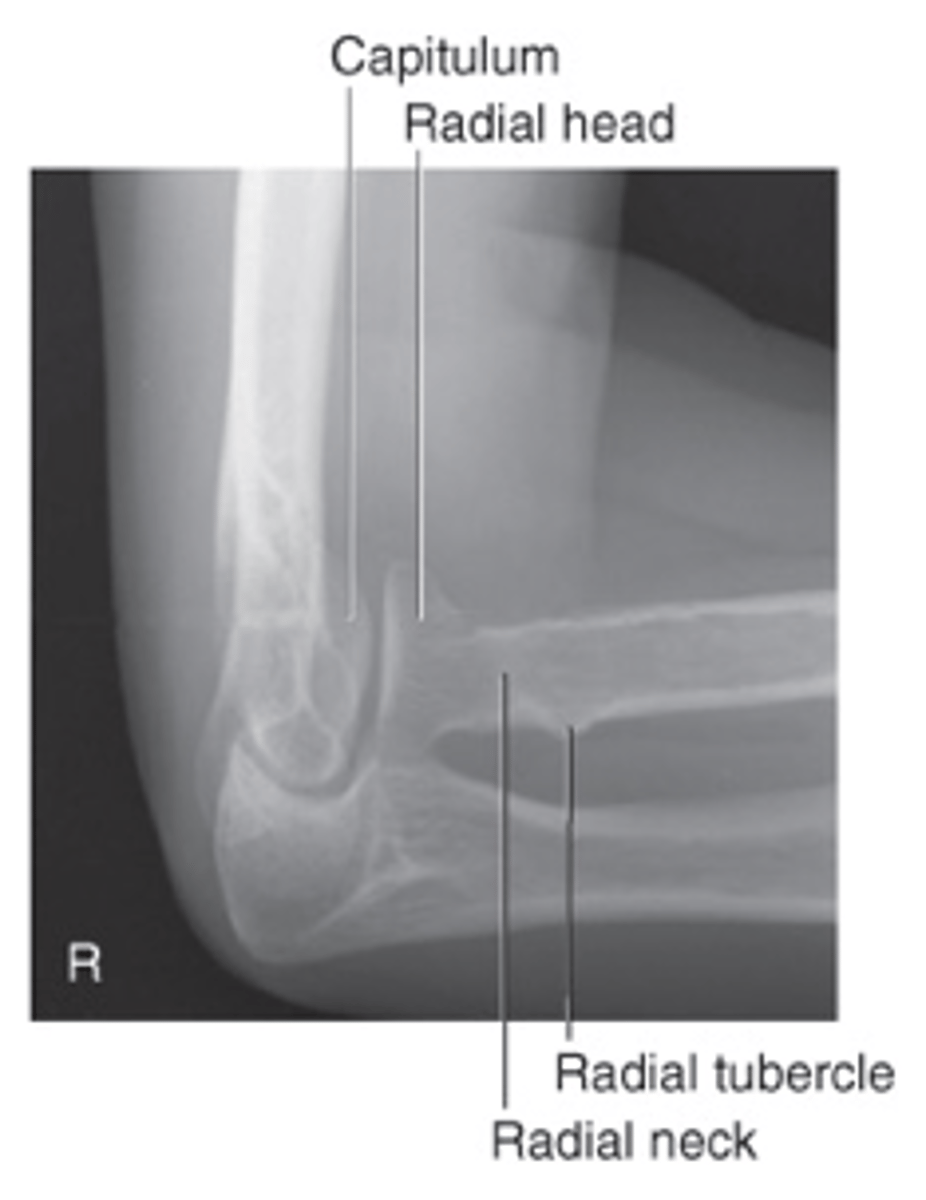

AP Elbow

AP elbow humerus parallel

AP elbow forearm parallel

AP Lateral (External) Oblique Elbow

AP medial (internal) oblique elbow

Lateral Elbow

Axial lateromedial for coronoid process elbow

Axial lateromedial for radial head elbow